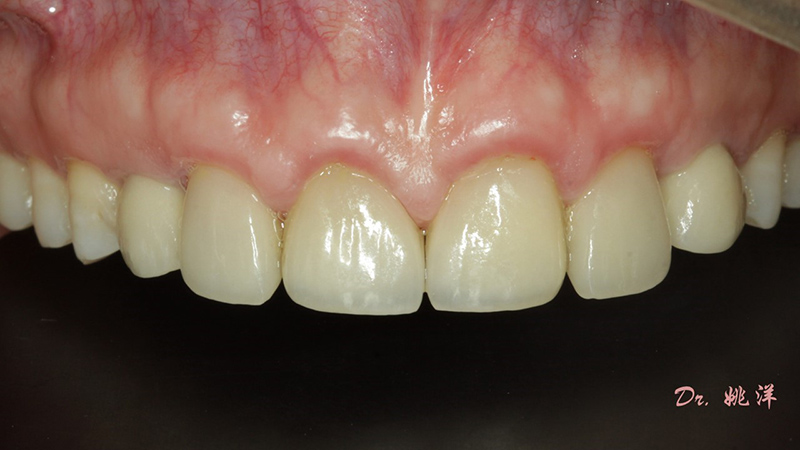

術(shù)后照片

恢復(fù)了正常的淺覆合淺覆蓋